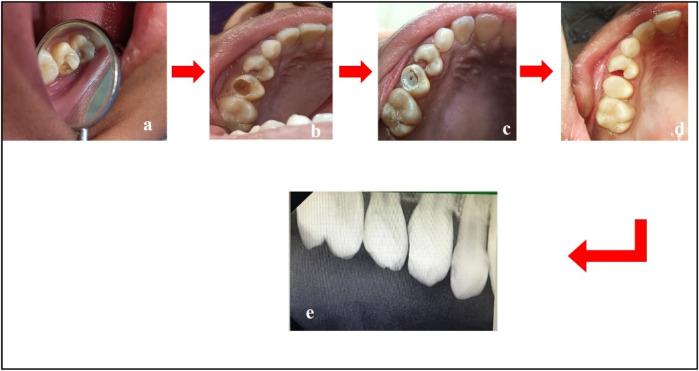

一名10岁女孩的萌出前牙内吸收:综述与病例报告

Pre-eruptive intracoronal resorption in a 10-year-old girl: a review and case report.

Pre-Eruptive Intracoronal Resorption (PEIR) is a pathological condition characterized by the resorption of dental tissues within the crown of an unerupted tooth. It is typically asymptomatic and is most often identified incidentally during radiographic examinations. The exact etiology of PEIR remains unclear, although various theories have been proposed, including developmental disturbances, trauma, and genetic factors. This article aims to provide a comprehensive review of PEIR, following the Case Report (CARE) checklist, to enhance understanding and awareness of this dental anomaly.

摘要